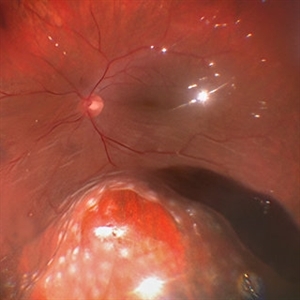

RPE rip in a case of Idiopathic polypoidal choroidopathy RPE rip in a case of Idiopathic polypoidal choroidopathyOct 23 2022 by Anjana Mirajkar, MS Ophthalmology Montage of Fluorescein angiography in a of 61 year old male with RPE rip in a case of Idiopathic Polypoidal Choroidopathy. Photographer: Dr. Anjana Mirajkar -Retina Foundation, Ahmedabad Condition/keywords: Idiopathic polypoidal choroidopathy, RPE rip